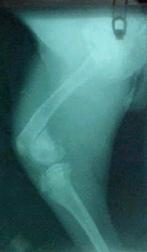

Cerinte suplimentare – examen radiologic (pentru articulatia scapulo-humerala)

Diagnostic – osteocondrita disecanta

Cerinte suplimentare – examen radiologic – articulatia cotului

Diagnostic fractura de proces anconat al ulnei